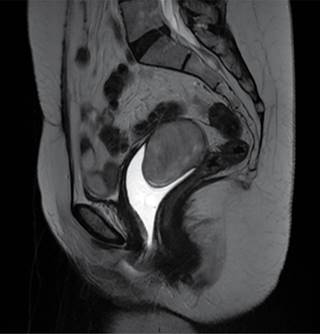

Se le realizó una resonancia magnética (RM) con medio de contraste, la cual mostró una imagen ovoidea de bordes regulares, que midió 5.6 × 3.6 cm en la cúpula vaginal (Figura 1). Sus estudios de laboratorio y marcadores tumorales estaban dentro de los parámetros normales. En la laparotomía exploradora se encontró un tumor de 7 × 6 cm, encapsulado, blanco nacarado y pediculado, que es dependiente de la cúpula vaginal pero que no invade los tejidos adyacentes (Figura 2).

Figura 1: Resonancia magnética (RM) de T2, donde se muestra un corte sagital con gel en conducto vaginal.

Radiológicamente, no hay un estudio de elección, pero muestran sólo intensidad heterogénea en T2 y con reforzamiento rápido no homogéneo con gadolinio.7